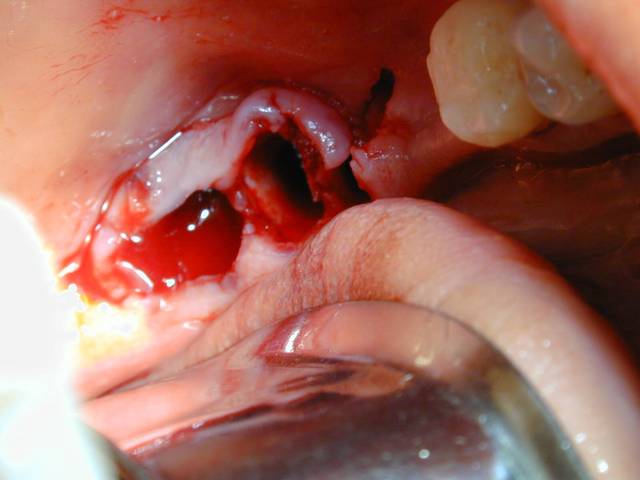

Dscn5362 rmoj2v - Eugenol

Dscn5003 twwkkj - Eugenol